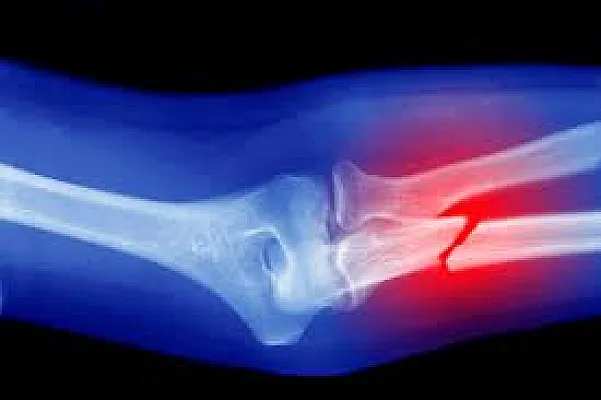

Çin kemik bilimsel araştırma Çinli bilim insanlarının geliştirdiği Bone-02 adlı biyolojik yapıştırıcı, kemik kırıklarını dakikalar içinde onararak aylar süren tedavi süreçlerini ortadan kaldırıyor.

Tıp dünyası, her geçen gün insan sağlığını ileriye taşıyacak yeni teknolojilerle tanışıyor. Cerrahiden biyoteknolojiye, nanoteknolojiden rejeneratif tıbba kadar birçok alanda yapılan çalışmalar, insanlığın yaşam kalitesini artırmayı hedefliyor. Bu yeniliklerden en dikkat çekici olanlardan biri ise, Çinli bilim insanlarının geliştirdiği ve “Bone-02” adı verilen biyolojik yapıştırıcı. Bu buluş, kemik kırıklarının tedavisinde devrim yaratabilecek bir potansiyele sahip. Çünkü Bone-02, kırıkları yalnızca birkaç dakika içinde onarabiliyor. Normal şartlarda aylar süren iyileşme süreçlerini ortadan kaldırarak hem hastalara büyük kolaylık sağlıyor hem de sağlık sistemine ciddi avantajlar sunuyor.

Klasik tedavi yöntemlerinde, bir kemik kırıldığında hastanın haftalarca alçıyla dolaşması ya da platin, vida ve çivilerle uzun bir cerrahi sürece girmesi gerekebiliyor. Bu süreç sadece fiziksel değil, psikolojik olarak da yıpratıcı olabiliyor. Üstelik enfeksiyon riski, ikinci ameliyat ihtiyacı ve günlük hayatın kısıtlanması da cabası. İşte tam da bu noktada devreye giren Bone-02, iyileşme sürecini hızlandırarak modern tıbbın uzun zamandır çözmeye çalıştığı büyük bir soruna çare sunuyor.

Bone-02, özel bir biyolojik yapıştırıcıdan oluşuyor ve kemik dokusunu sadece üç dakika içerisinde birbirine sabitleyebiliyor. Bu da demek oluyor ki, örneğin bir bilek kırığı yaşayan hasta, uzun bir ameliyat süreci geçirmeden, yalnızca küçük bir kesiden yapılan enjeksiyonla tedavi edilebiliyor. İyileşme sürecinde kullanılan yapıştırıcı, kemikle bütünleşiyor ve zamanla vücut tarafından emiliyor. Yani kalıcı bir yabancı madde bırakmıyor. Bu özelliği sayesinde ikinci bir ameliyata gerek duyulmuyor.